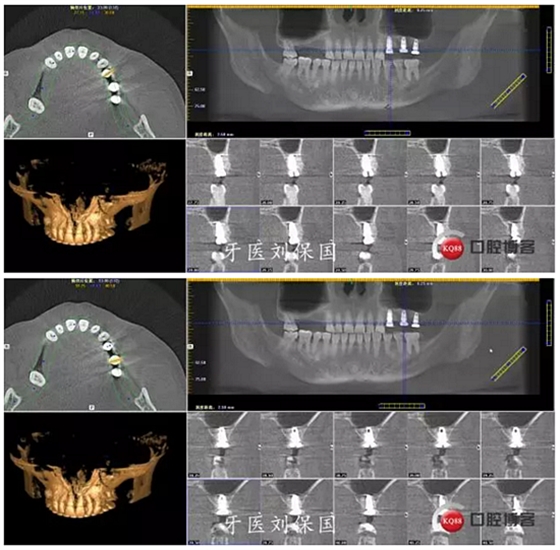

1.術(shù)前CT:

3.術(shù)后CT: